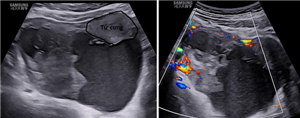

CLS: Thai ngoài tử cung mạn tính-huyết tụ thành nang

Thai ngoài tử cung mạn tính (TNTCMT) là một thể hiếm gặp của thai ngoài tử cung ở tai vòi